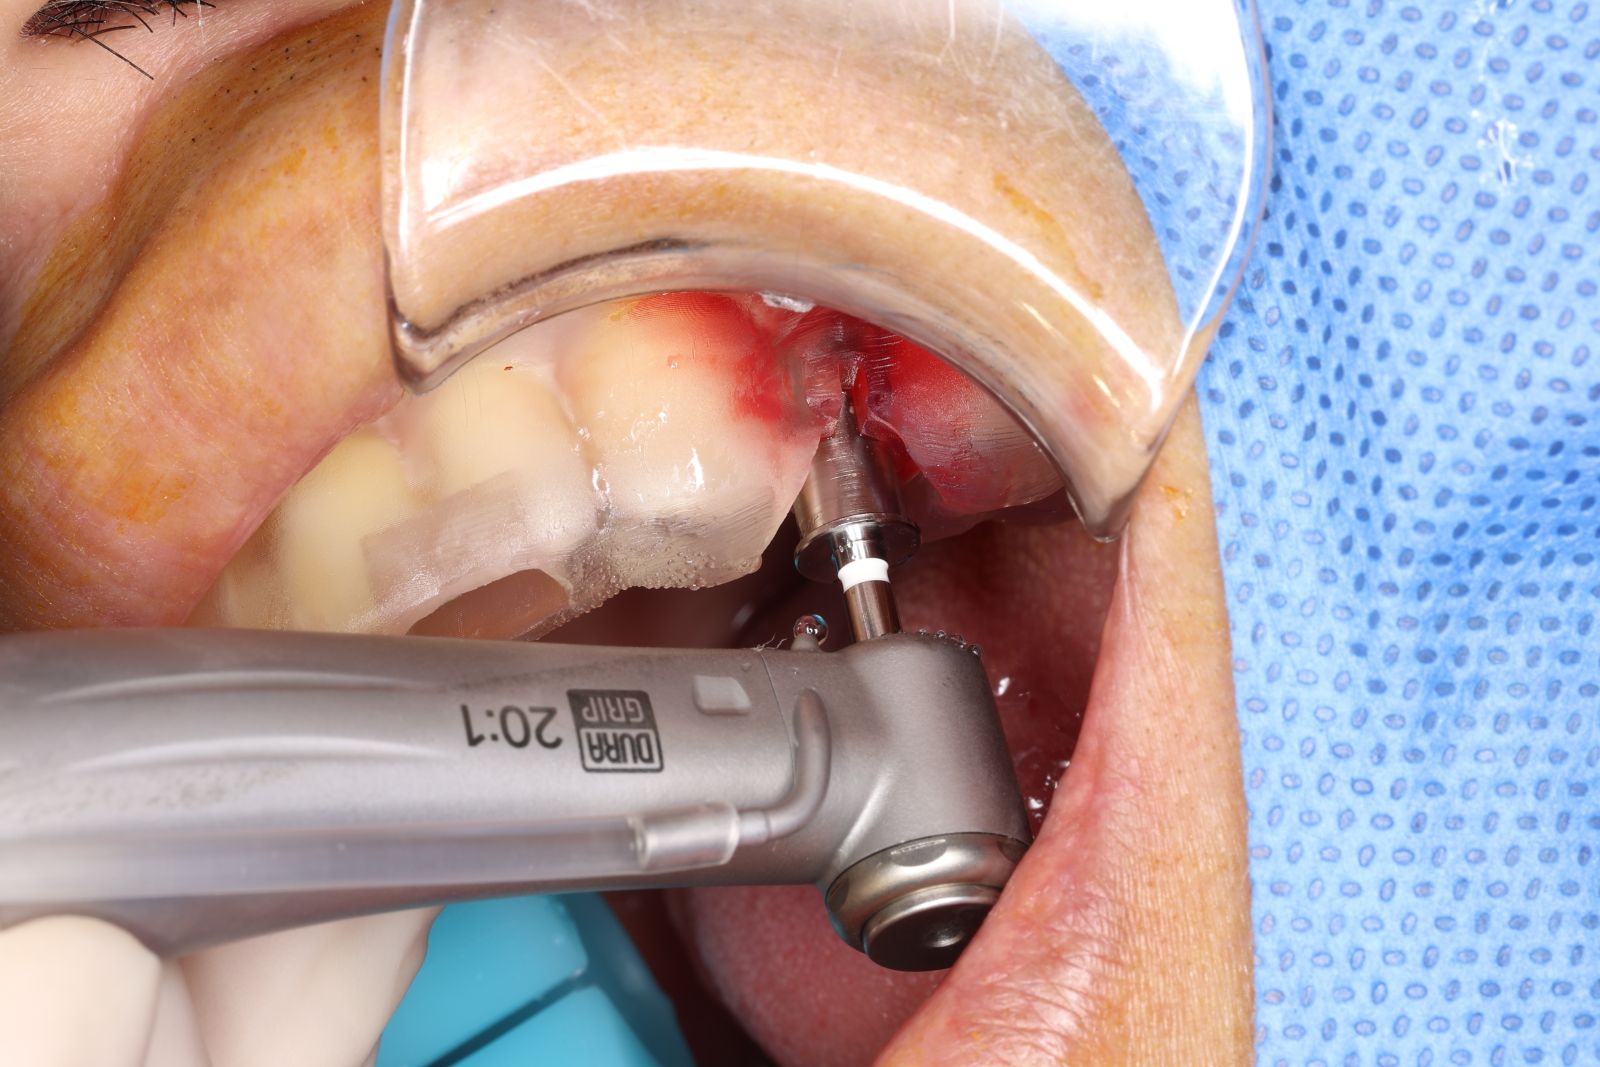

【 案 例 三 】

- 手術過程,在植入植體前先用導板定位,確認植牙位置及角度。使用導板讓傷口範圍縮小。

- 手術後傷口小無需縫合,也不用再來拆線,幾乎不會腫脹出血,術後恢復期舒適快速!

- 待3.4個月後裝上全陶瓷牙冠完成植牙療程。整個療程過程輕鬆。